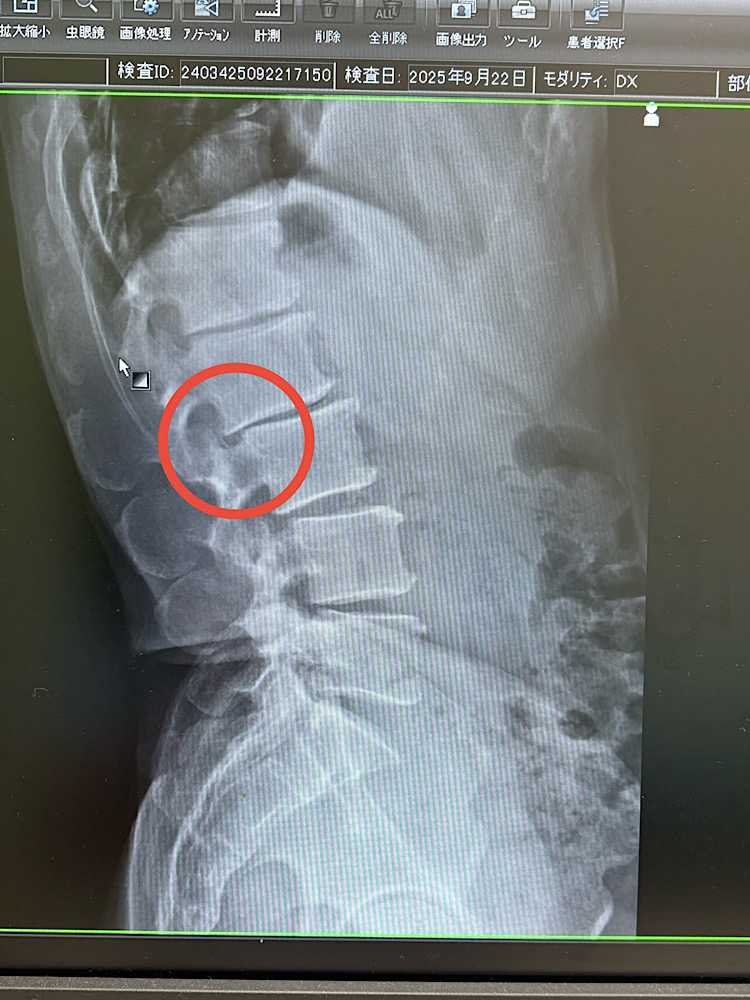

また滑り症との戦いが始まってしまいました(笑)調子が良くて補強も充実させていこうと、新たにタバタ式サーキットトレーニングと縄跳びを始めました。何という名前かわかりませんが、ジャンピングスクワットみたいなやつが負担がかかったようです。数日、「ちょっと負荷かけたなぁ」と張ってる様子の状態で、重いものを背負う瞬間にギックリ腰っぽいのをやってしまいました。その後の対策をしっかりできたので大きな痛みは早めに引いたのですが、張りや違和感が消えず医者に行ったところ、画像のように滑っていました(笑)先生によると、無理しなければそのうち戻る…とのことで、薬もリハビリもなくていいようです。微妙に走れたりするのですが、3日に1回5キロぐらいで次の日は背中から腰がパンパン。また闘いが始まってしまいました。そして早くも来シーズン終了です(笑)#腰椎滑り症#がっかりヘンププロテイン麻の実 無添加 ソイ プロテイン アミノ酸 オーガニック タンパク質 植物性プロテイン